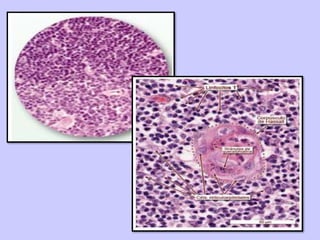

CORPUSCULO

DE HASSALL

• Masa concéntrica de

células escamosas,

unidas por desmosomas

y con haces de

filamentos intermedios.

• Formado principalmente

por células epiteliales

tipo 6, que reaccionan

con anticuerpos

antiepidérmicos.

• Región central

formada por

células

anucleadas que

pueden degenerar

o calcificarse.

• Tiene una región

periférica formada

por células planas.

• No se sabe su

función.

CORPÚSCULO DE

HASSALL